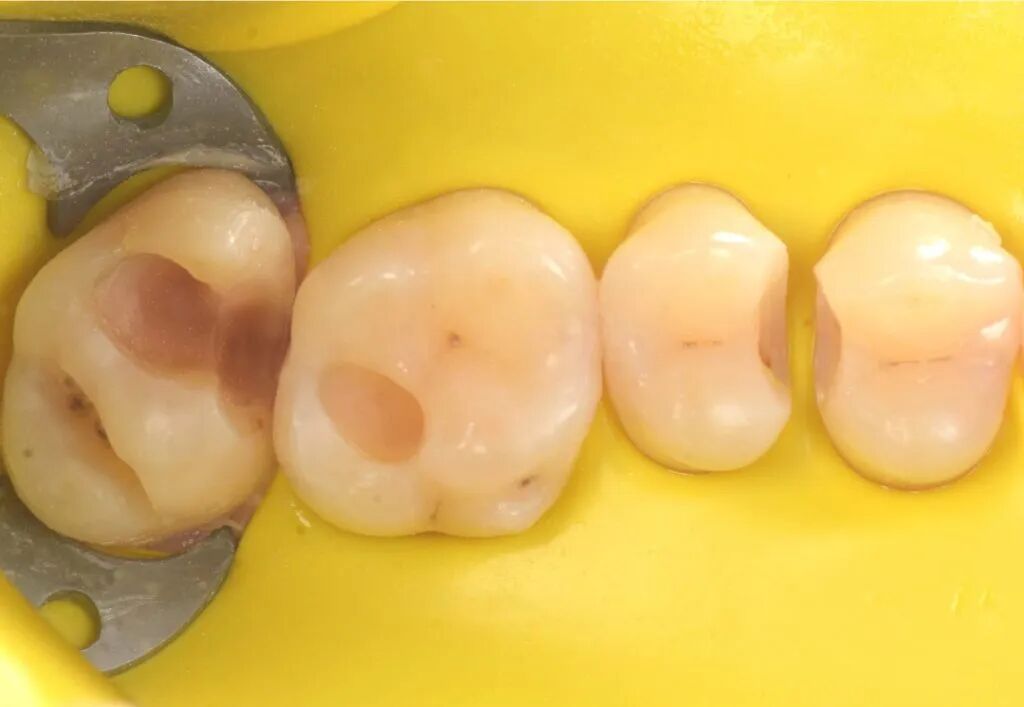

图4. 清除龋损后,29μm氧化铝喷砂清理洞壁、洞缘。

图5. 龋洞清理完成。准备酸蚀和黏结。

图9. 放置成形片和成形片夹。

图11. 光固化垫底材料置于27窝洞最深处。

图13. 垫底后准备充填修复。